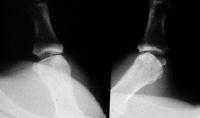

Questionable cases can be evaluated with stress Xrays to determine just how far off track the joint deviates:

Click for larger image

Films are compared with and without stress. This thumb not only translates radially, but "opens up", indicating a complete ligament tear.

This thumb translates about 40% to the side, but does not open up: still a complete disruption.